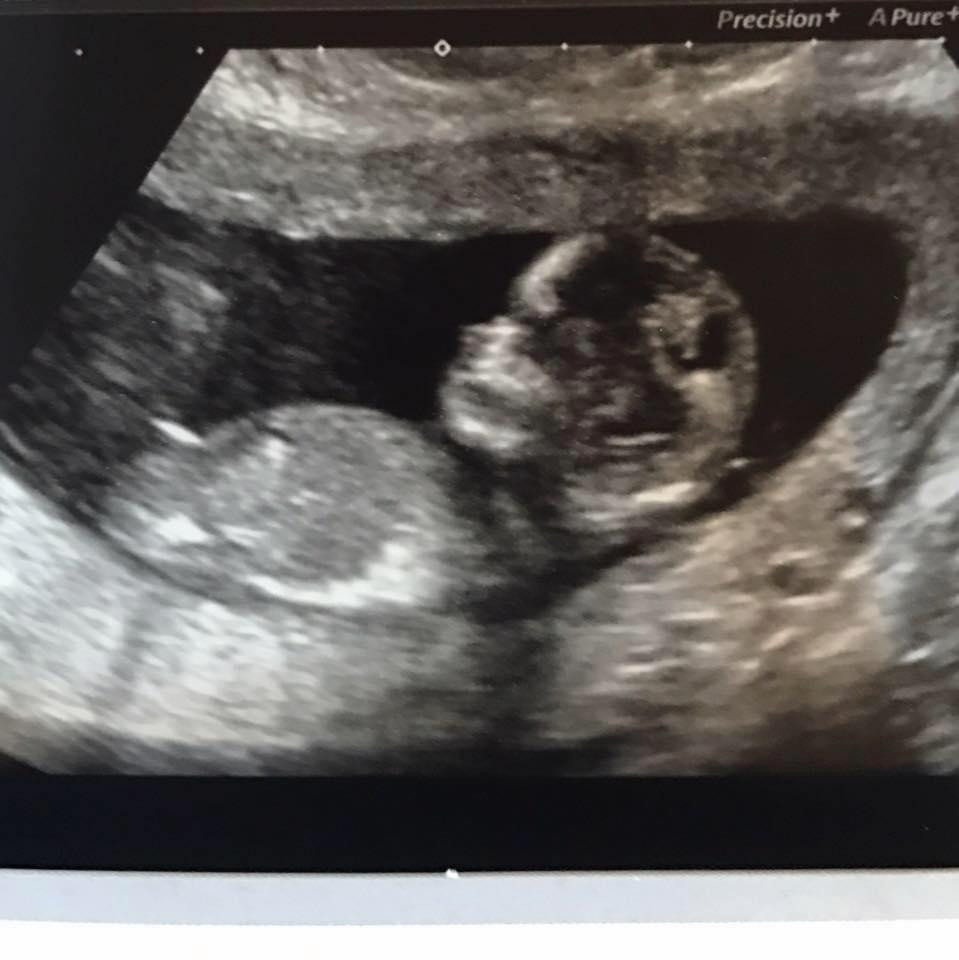

Bé Archie khi ở trong bụng mẹ